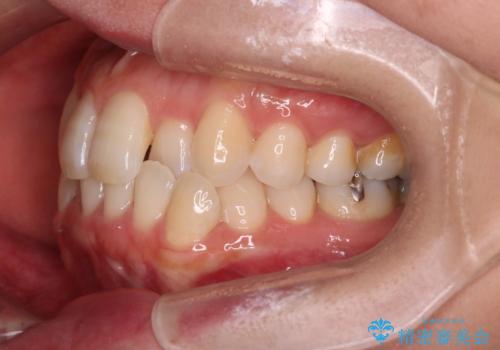

【インビザライン】前歯の凸凹をなおしたい

- 前歯の凸凹を主訴に来院されました。

上顎の急速拡大を行なったのちインビザラインにて治療を行なっております。

今回のケースは後戻りのリスクを低くし、またディスキング量を減らすために上顎の急速拡大を行なっております。